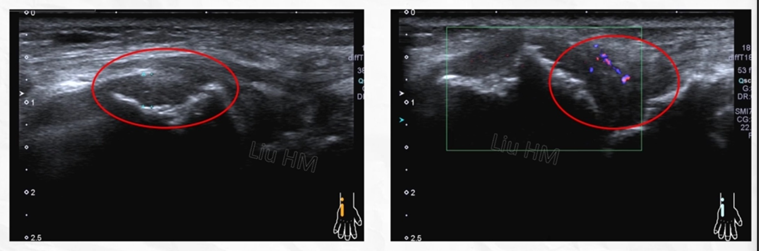

类风湿关节炎

(腕关节滑膜增厚,血管翳形成,关节软骨面不光滑,骨皮质呈虫蚀状破坏)